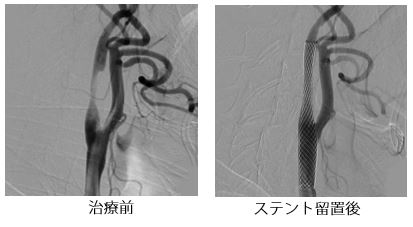

動脈硬化により脳へ血液を送る頸動脈が狭窄する病気です。狭窄が高度な場合は、将来的な脳梗塞の予防のために、カテーテル治療(頸動脈ステント留置術:CAS)や外科治療(頸動脈内膜剥離術:CEA)を行います。どちらの治療法を行うかに関しては、狭窄のタイプや全身状態を詳しく調べ、個々の患者さんに適切な方法を選ぶようにしています。